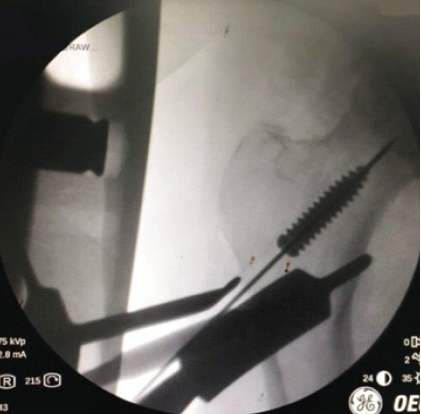

This did not work as force is required to mate the screwdriver tip to the screw head, which would lead to further burial of the screw. Subsequently, a guide wire was bent to create a hook at the end and insertion across the interference was attempted (Fig. 3).

Figure 3: Attempting removal with a hooked guide wire.

This proved to be challenging as a large hook would not go across the screw and a small hook would not be able to get adequate purchase at the screw tip to be able to pull it back [6,7].